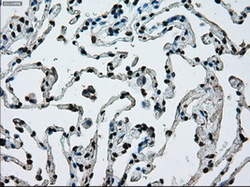

- Submitted by

- LSBio (provider)

- Enhanced method

- Genetic validation

- Main image

- Experimental details

- Immunohistochemical staining of paraffin-embedded lung tissue using anti-ERCC1 mouse monoclonal antibody. (Dilution 1:50).